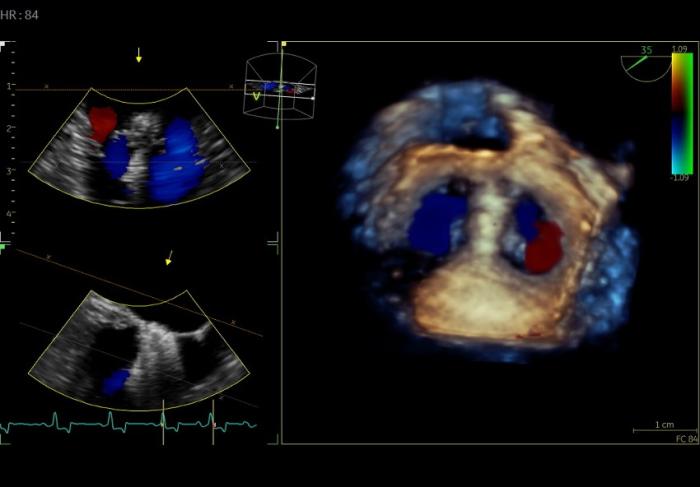

El procedimiento quirúrgico se realizó bajo anestesia general y con guía ecocardiográfica transesofágica tridimensional (TEE-3D). Se llevó a cabo mediante exposición del ápex cardíaco mediante una mínima toracotomía izquierda en el séptimo espacio intercostal. Seguidamente se realizó pericardiectomía con exposición de saco pericárdico y epicardio para crear un segundo campo quirúrgico mediante tracción cardíaca. Posteriormente, tras localizar el lugar de punción a nivel del ápex cardíaco mediante visualización directa y ecocardiográfica en 3D, se colocaron dos suturas en la zona del ápex con refuerzo de tejido Goretex y colágeno bovino (Figura 1).

Se realizó la punción transapical ecoguiada y posterior intercambio a introductor de 14 French. Se introdujo un catéter introductor vascular de 6Fr que permitió colocar un dispositivo de nitinol con el extremo distal de forma esférica para poder avanzar el catéter de 14Fr hasta el atrio izquierdo. Se retiró el catéter guía y el catéter de 6Fr y se introdujo el dispositivo V-Clamp con su primera apertura en posición atrial y segunda en posición ventricular. Tras confirmación mediante TEE-3D y estudio Doppler color de la correcta posición de dispositivo en la zona central de la válvula mitral, se procedió al cierre, toma de medidas de seguridad pre-liberación y liberación del mismo. Finalmente, una vez liberado el dispositivo se confirmó la correcta posición, con una reducción intraquirúrgica de la RM de 78 %, calculada en base al porcentaje del volumen regurgitante en el atrio izquierdo (Figura 2).